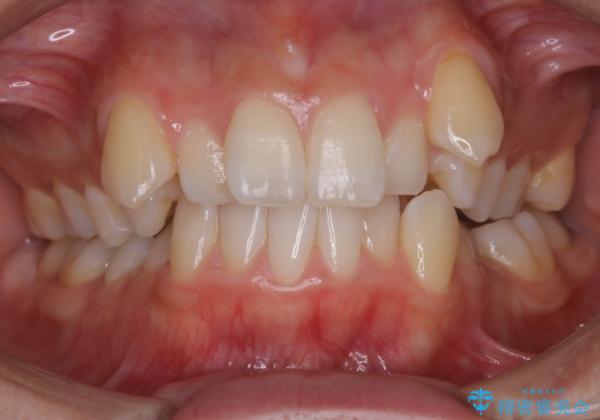

- 上顎の八重歯が気になるとのことで来院されました。

左側のかみ合わせは、歯1本分かみ合わせが前にずれていました。上顎左右の奥歯を2本抜歯しています。

下顎は、歯の側面を少し削ることで歯並びを整えました。

八重歯でがたつきは重度でしたが、きれいな歯並びにすることができました。

がたつきだけでなく、奥歯の噛み合わせのずれの調整もしっかり行いました。